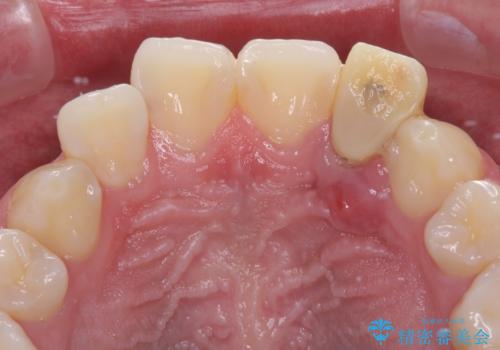

- 他院で前歯の抜歯が必要と言われたとのことで来院された患者様です。

過去にぶつけたことで神経組織が壊死してしまったようで、その後むし歯が進行して歯肉深いところにまで進んでいる状態でした。

まずは部分矯正により歯を牽引し、歯肉や歯槽骨の位置を調整するために歯周外科処置を行い、治癒を待ってオールセラミッククラウンにて補綴治療を行うこととしました。